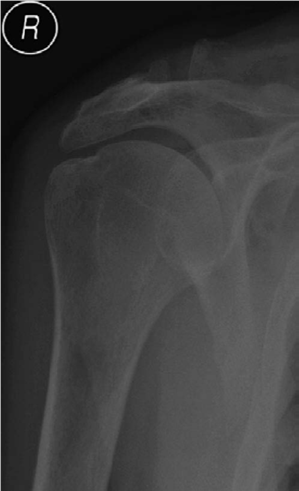

Shoulder and elbow structured oral examination question3 EXAMINER : This is a radiograph of right shoulder of…